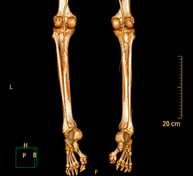

Prova diagnòstica no invasiva que consisteix en l'estudi vascular del sector aorto-ilíac i dels vasos arterials d'ambdues extremitats inferiors i l'obtenció d'imatges d'alta definició anatòmica mitjançant l'ús d'un equip de TC Multidetector d'última generació i de contrast iodat. La qualitat de les imatges permet realitzar reconstruccions en 2D i 3D gràcies a estacions de treball especialitzades en l'estudi arterial.

Prova diagnòstica no invasiva que consisteix en l'estudi de vascular del sector aorto-ílíac i dels vasos arterials d'ambdues extremitats inferiors amb l'obtenció d'imatges d'alta definició anatòmica mitjançant l'ús d'un equip de TC (Tomografia Computaritzada) i contrast iodat. La qualitat de les imatges permet realitzar reconstruccions en 2D i 3D gràcies a estacions de treball especialitzades en l'estudi arterial.